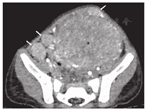

CT平扫上可见肿瘤呈不均匀等/低于肌肉密度,其中3例肿瘤于中心区域可观察到斑片样低密度区,2例低密度区呈小灶状或条片状散在分布,增强后不强化或仅呈轻度强化,CT值升高均<10 HU,病变周围部分可见动脉期明显强化,CT值升高约30~79 HU,静脉期呈持续强化,CT值继续升高8~36 HU,2例肾脏病变者加做了延迟期扫描,可见病变周围部分有强化减低表现,1例出现向心性强化(图1)。1例病变平扫密度较均匀,未观察到明显密度减低区,增强后病灶仍以周边强化为主,CT值升高约52 HU,中心区域轻度强化(CT值升高约17 HU)呈相对低密度区。5例肿瘤内可见迂曲增粗血管影,且多分布在肿瘤周边部分(图2)。2例病灶内可见点状及沙砾样钙化。

在增强CT图像中,PEComa常在动脉期表现出周边分布的明显强化,这表明PEComa是一种富血管性肿瘤,且供血微血管常围绕肿瘤周围存在,这一"周边强化"的影像学特征可能对PEComa的鉴别诊断很有价值[3,11]。由于病变内拥有多种不同的细胞成分,故多呈不均匀强化,5例肿瘤中心的低密度不强化区代表了瘤内的大面积坏死、液化部分,其中3例肿瘤切除后得到了病理证实。1例病变平扫密度较均匀,增强后仍以周边强化为主,中心区域轻度强化呈相对低密度区,可能与其平滑肌结构或其他少血管成分有关。对本组病例的CT动脉期图像进行最大密度投影(MIP)重建可清晰显示肿瘤内迂曲增粗的血管,可见5例PEComa的血管分布于病变边缘,呈包绕状,这与大多数肿瘤血管常延伸至病变内有所不同。静脉期多数PEComa在静脉期呈持续强化,延迟期病变周围部分出现强化减低,1例病变出现类似"血管瘤"的向心性强化,更说明了该病变血供丰富。